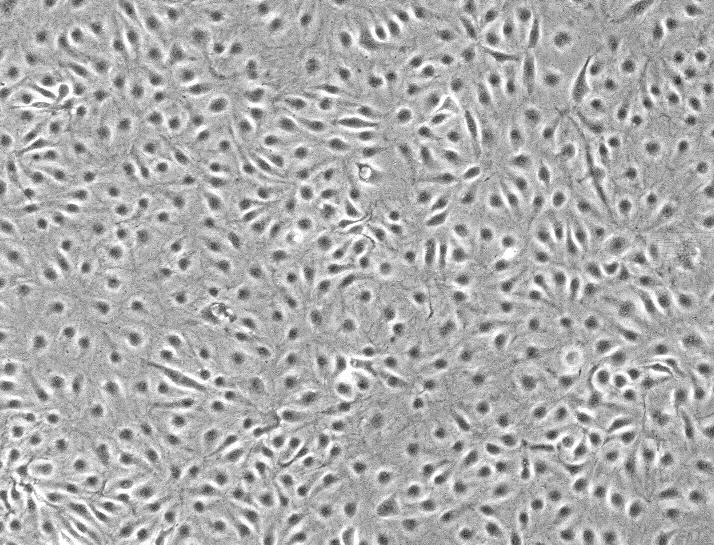

大鼠脑血管内皮细胞 ,RBE4特性:

1)种属:大鼠

2)形态:贴壁

3)含量:>1x10^6 个/mL

文献和实验体外培养模型已被广泛应用于血脑屏障的研究、脑血管疾病的病理生理及分子生物学研究、新药筛选、脑微血管内皮细胞生理生化及药理学研究等领域。而大多数体内实验采用大鼠为动物模型,而且大鼠具有较多的细胞生物学研究所需的抗体可用,因此进行大鼠脑微血管内皮细胞的培养具有重要的意义。自从Panula等[2]首次成功培养大鼠脑微血管内皮细胞以来,国内外有关大鼠脑微血管内皮细胞的分离和培养方法已有较多的报道,我们发现国内的方法多以组织匀浆、两次尼龙网过滤分离脑微血管段为主[3,4],也有采用酶消化、梯度离心及尼龙网过滤

本人总结了下大鼠内皮细胞的培养方案 一,消化法。优点:获得的细胞比其他方法纯。缺点:获得细胞比较少。 常见问题及解决方法:1.消化的时间不好控制时,建议大家分两段时间消化,消化30分钟时收取消化液放入一个离心管,30分到45分钟段收集的放入另一离心管,离心后看看第二管是否有杂细胞,若没有就把两管混合用,若有就只用第一管的。2.消化液,我的经验是5份0.2%胶原酶和1份0.125%胰酶。3.若很难消化时,可以磁力搅拌消化。注意消化法时结扎一定要紧! 二,植快法。优点:获得细胞